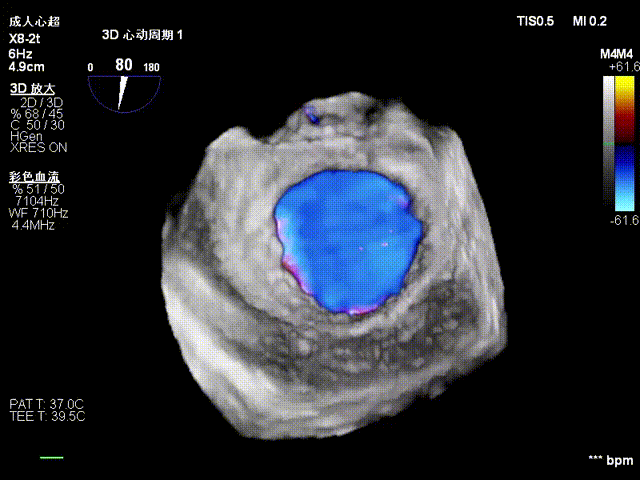

3D color Doppler

Mitral valve Zone 2

Color Doppler of Mitral valve Zone 2

Tricuspid Valve Annuloplasty Stage:Subsequently, via the right internal jugular vein approach, the K-clip® transcatheter tricuspid valve annuloplasty system was delivered to the right atrium. With the assistance of three-dimensional ultrasound stereoscopic views, a 12T clip was successfully implanted at the posteroseptal commissural annulus of the tricuspid valve, and a 14T clip at the anteroposterior commissural annulus, achieving effective constriction of the dilated annulus. Immediate postoperative assessment demonstrated that tricuspid regurgitation was improved from severe (4+) to mild (1+) instantaneously.

1.Intraoperative baseline assessment of regurgitation severity

2.Placement of large sheath and delivery system under ultrasound guidance

3.Steer and rotate the delivery system to target the lesion, and implant the anchor screw via the 3D MPR plane

4.Land the clamping arms after orientation adjustment, and close the clamping arms slowly

5.Perform the same procedure for the second clip; the clip morphology is stable under 3D imaging